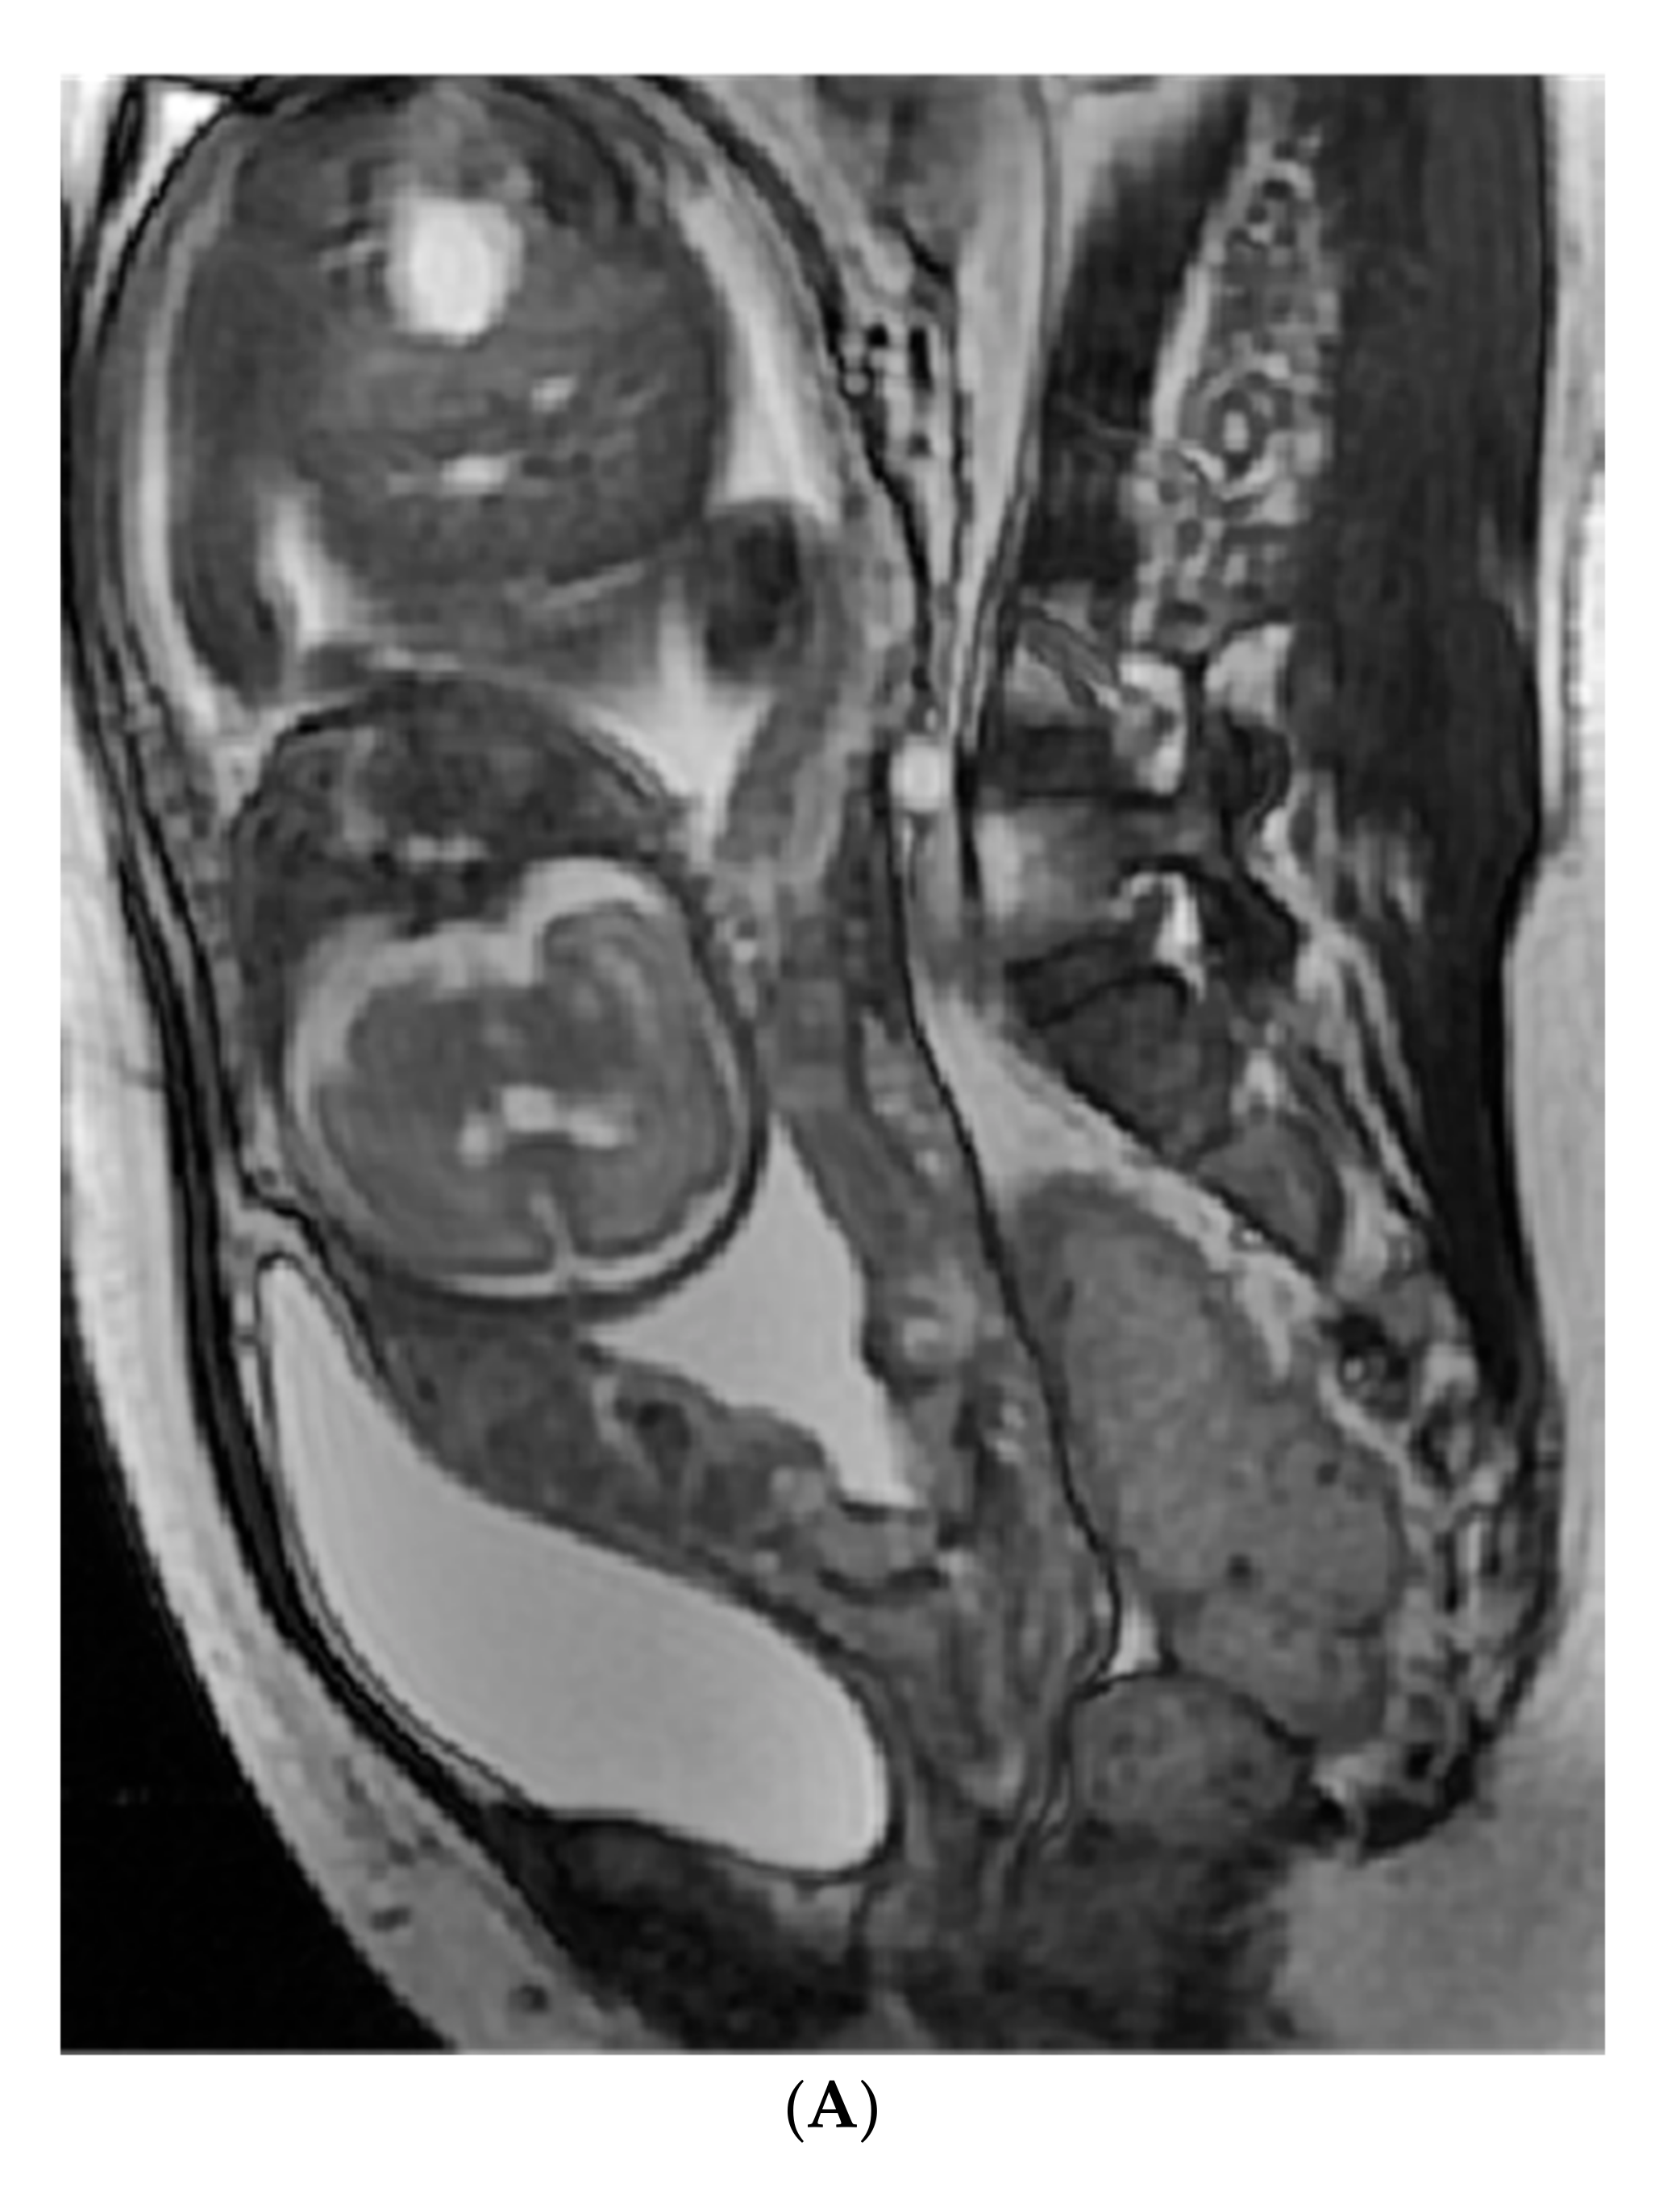

4.4.1. Image Analysis and Segment